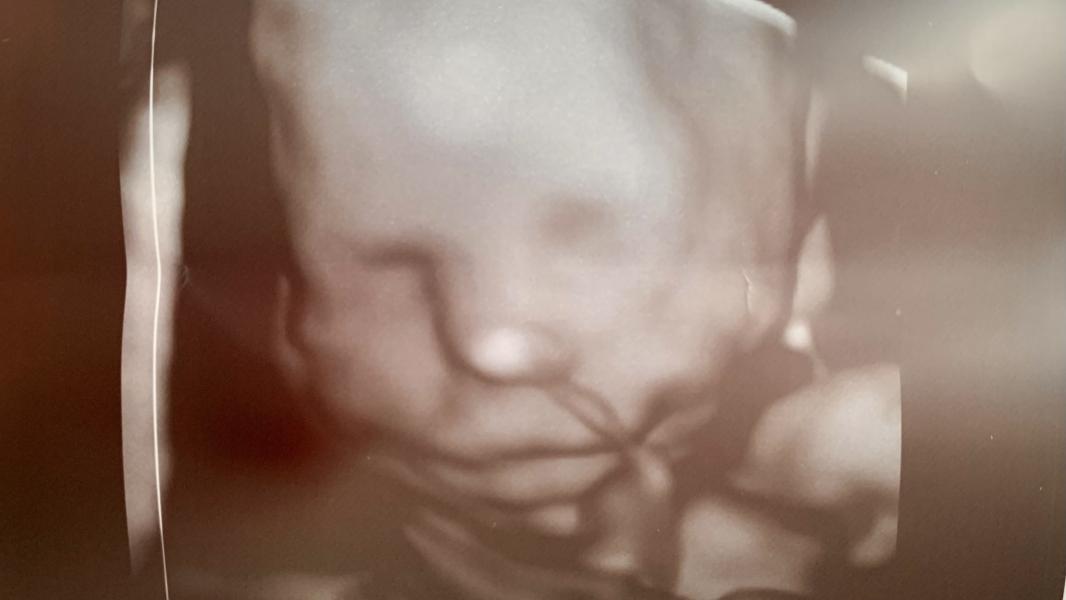

Наш маленький губастик 🌸

14.05.2024